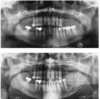

Panoramaschichtaufnahme.

Zystischer Prozess im Unterkiefer links mit

Lagebeziehung zum wurzelgefüllten Zahn 37.

Histologie: radikuläre Zyste